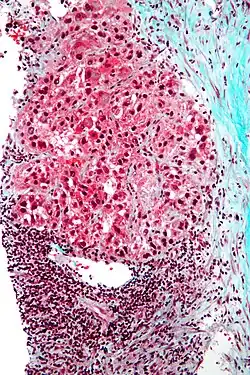

Pathology

Micrograph of hepatocellular carcinoma. Liver biopsy. Trichrome stain

Macroscopically, liver cancer appears as a nodular or infiltrative tumor. The nodular type may be solitary (large mass) or multiple (when developed as a complication of cirrhosis). Tumor nodules are round to oval, gray or green (if the tumor produces bile), well circumscribed but not encapsulated. The diffuse type is poorly circumscribed and infiltrates the portal veins, or the hepatic veins (rarely).[20]

Microscopically, the four architectural and cytological types (patterns) of hepatocellular carcinoma are: fibrolamellar, pseudoglandular (adenoid), pleomorphic (giant cell), and clear cell. In well-differentiated forms, tumor cells resemble hepatocytes, form trabeculae, cords, and nests, and may contain bile pigment in the cytoplasm. In poorly differentiated forms, malignant epithelial cells are discohesive, pleomorphic, anaplastic, and giant. The tumor has a scant stroma and central necrosis because of the poor vascularization.[46] A fifth form – lymphoepithelioma like hepatocellular carcinoma – has also been described.[47][48]